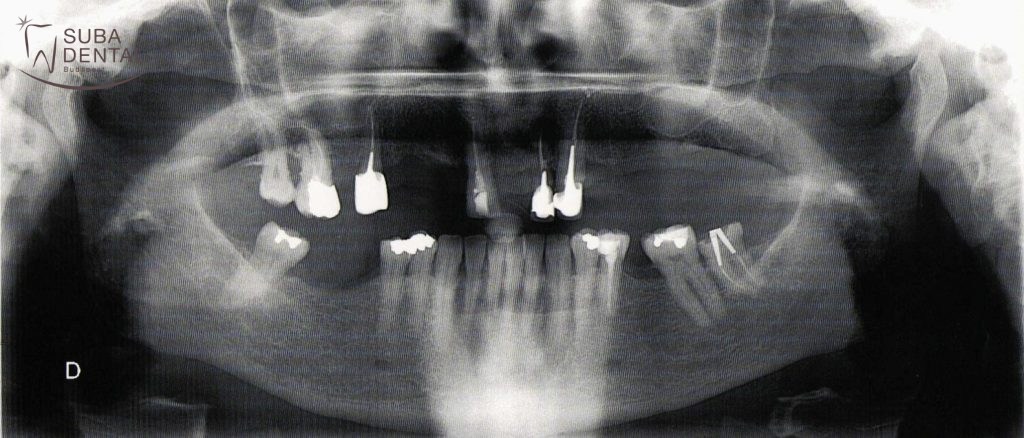

Az első konzultáció alkalmával a panorámaröntgen alapján alaposan megvizsgáltuk a fogak állapotát. CBCT (Cone beam computed tomography) felvétel alapján pontosan láthatóvá vált, hogy a csontkínálat megfelelő ahhoz, hogy az hiányzó jobb alsó őrlőket implantátumokkal pótoljuk. A bal felső régióban viszont az implantátumokkal való pótlás csak csontpótlással (sinus lift) lehetséges, melyet páciensünk nem szeretett volna.

Panoráma röntgen, melyet a páciens hozott magára az első konzultációra